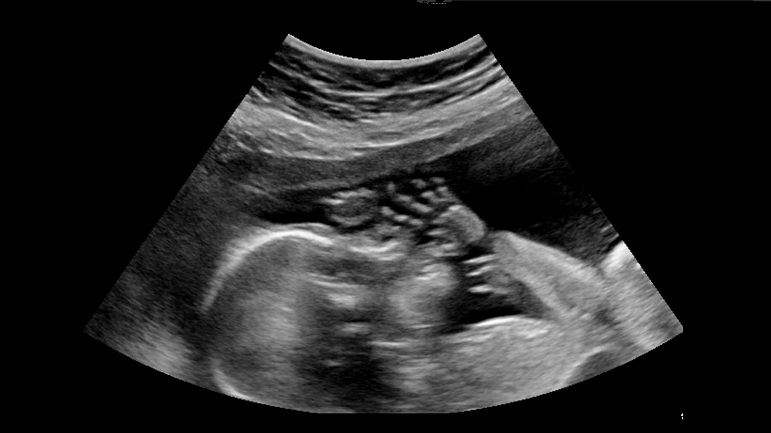

تتساءل النّسوة الحوامل عن مسألة صومهنّ في شهر رمضان المبارك، وهل يرخّص لهنّ بالإفطار، وما الّذي يترتّب على ذلك من أحكام شرعيّة؟!

ولاستطلاع الموضوع، نعرض لآراء جملة من العلماء تعرّضوا لهذه المسألة الحسّاسة، والتي هي موضع ابتلاء النساء الحوامل في شهر رمضان المبارك..